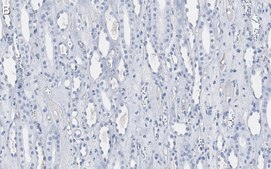

Immunohistochemistry (Paraffin) Analysis: A 1:100 dilution from a representative lot detected Atg5 in human kidney tissue sections.